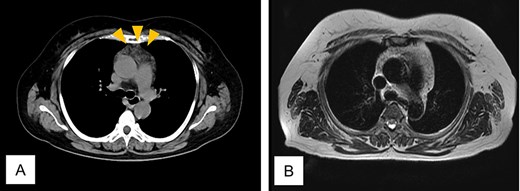

Twenty-four months after completing chemotherapy, CT revealed an anterior mediastinal mass (Fig. 4A). Chest magnetic resonance imaging (MRI) demonstrated no malignant features (Fig. 4B). A diagnosis of thymic hyperplasia was made.

Computed tomogram and magnetic resonance image of Case 2. (A) Chest computed tomogram shows a 4 x 3 cm anterior mediastinal mass with increased fat attenuation (arrowhead). (B) T2-weighted magnetic resonance image of the chest shows heterogeneous fatty signal within the thymus, but no solid component is observed.